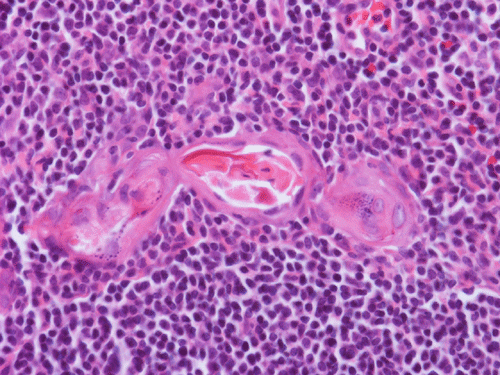

Histopathology: The lesion is encapulated cystic structure with the wall lined by nodules of lymphoid tissue (Panel A  and B) that are devoid of any evidence of hematopoiecic malignancy. Within this lymphoid tissue are small pink islands (Arrow in Panel C) and on higher magnification (Panel D) these islands are squamous cell nests. These islands are Hassell corpuscles and the lymphoid tissue is in fact thymic tissue. The cyst appears to have sustained repeated hemorrages. Both recent hemorrhage (Panel E) and cholesterol clefts consistent with resolved hemorrhage (Panel F) are present.